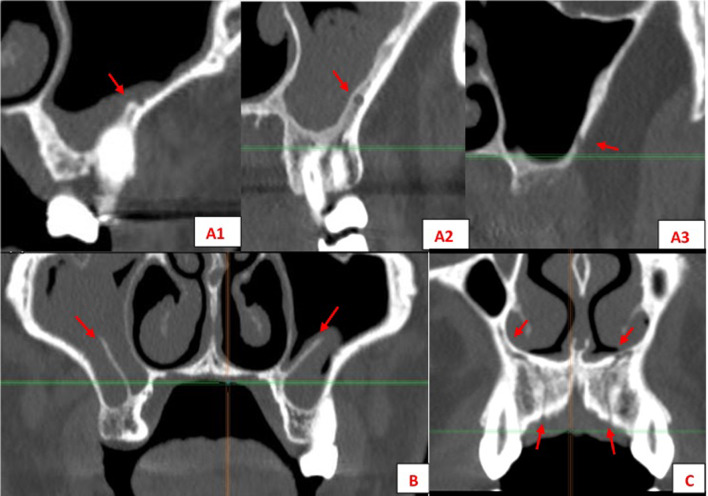

Fig. 4.

Viewing and measuring the PSAA in MPR format (axial and sagittal planes). Horizontal and vertical measures related to PSAA

Fig. 5.

Left: Intrasinus (I) PSAA. Right: intraosseous (II) PSAA